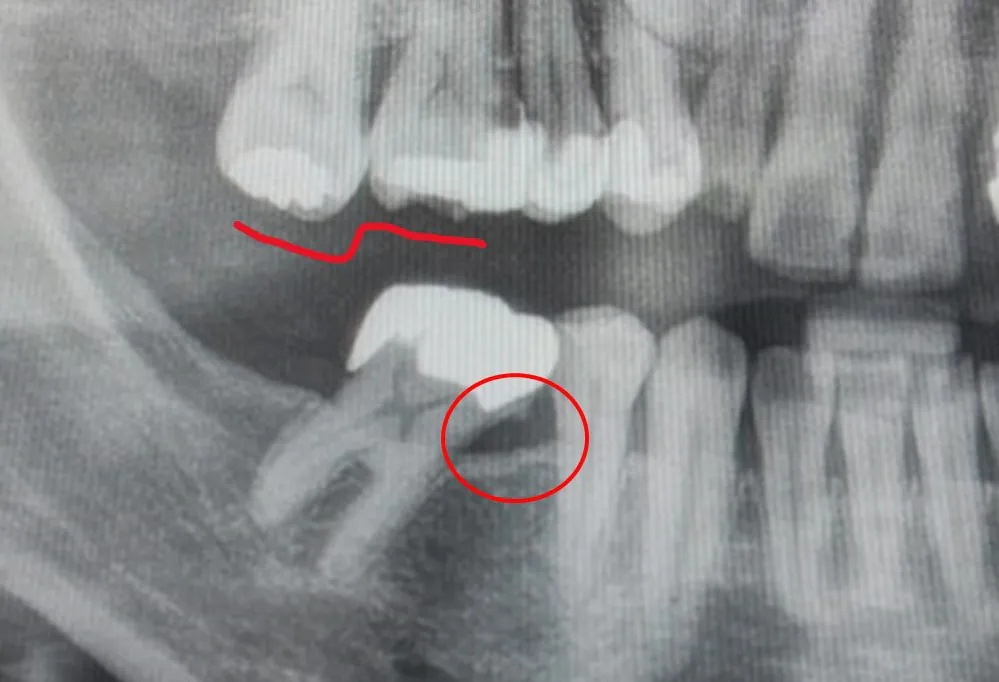

時間とともに対合歯の挺出(スーパーループション)や、欠損隣在歯の傾斜・移動、食片圧入、咬合変化が生じやすく、後の治療が複雑化・高額化する傾向があります。

- 起こりうること:対合歯挺出/隣在歯の傾斜・空隙/咬耗・咀嚼効率低下/顎堤の骨吸収

何もしないと…対合歯が挺出して咬合が崩れます

欠損部と咬み合う歯は、接触が失われると時間経過で挺出・傾斜・回転しやすく、咬合平面の乱れや清掃不良を招きがちです。

※図はイメージです。実際の対処法は症例により異なります。